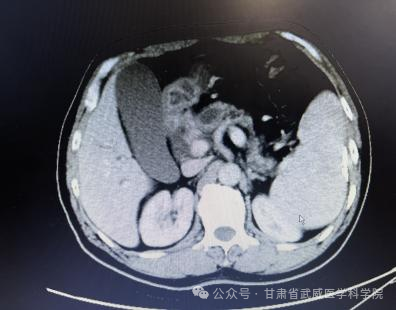

确诊时腹部CT资料